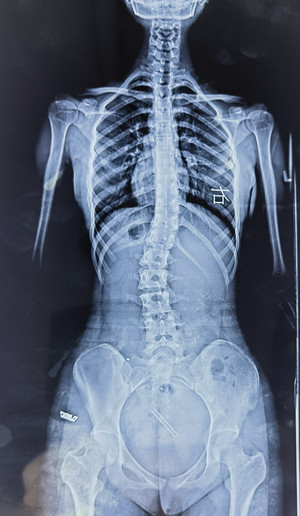

脊柱側彎拍X片

我的孩子可能脊柱側彎了,想拍一個 “ 站立式全脊柱正側位X片 ” 。

您也可以給醫(yī)生看上圖,問下醫(yī)生能不能拍這樣的X片(并不是所有醫(yī)院都有能力拍這樣的X片)。